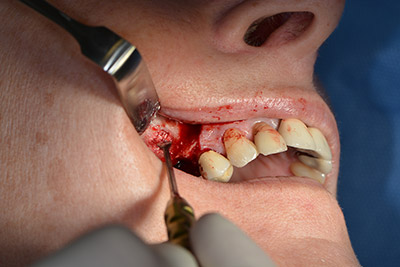

Procedura chirurgica per l'impianto

L'incisione classica (rilascio crestale e buccale) e la preparazione del lembo mucoperiosteo favoriscono un'ottima panoramica.

In questo caso vengono usati impianti di tipo SKY (bredent). Il loro protocollo chirurgico specifica una perforazione pilota di circa 1200 rpm (fig. 9).